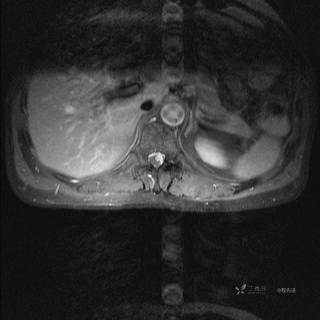

MR

T2

T2压脂

T1

T1增强

T1增强冠状位

T1增强横断位